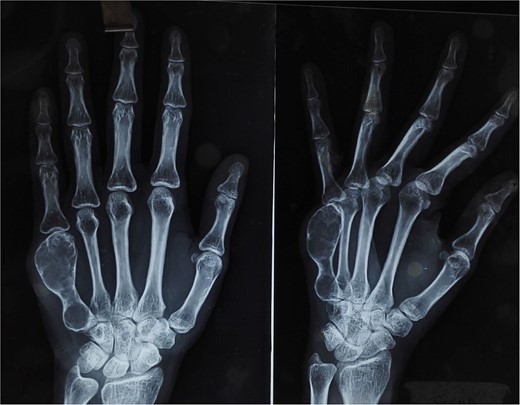

At 2 years postoperatively, the patient showed excellent functional outcomes. Radiographs demonstrated a stable MCP joint with well-preserved joint space, indicating successful graft incorporation (Fig. 3). Donor site radiographs at 2 years showed appropriate spacing between the third and fifth metatarsals with no evidence of arch collapse or stress reaction in the adjacent bones (Fig. 4). The patient achieved an active MCP joint range of motion of 0–80 deg (Fig. 5).